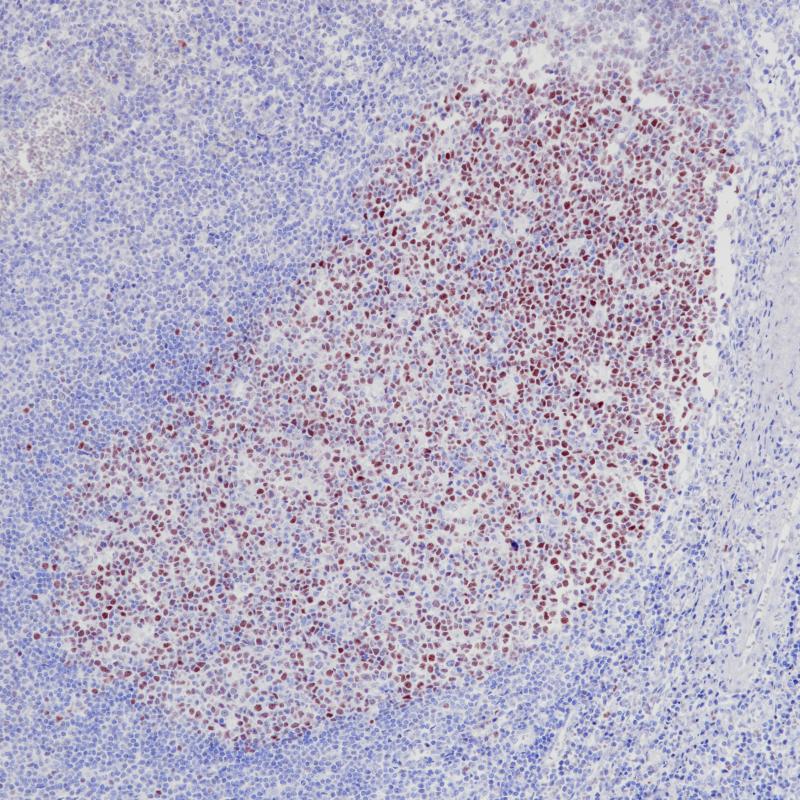

Bcl-6是一个转录调控基因,编码706氨基酸核锌指蛋白。丝裂原活化的蛋白激酶Erk1和Erk2,而不是JNK,在多个位点磷酸化BCL6。BCL6 Ser333和Ser343位点的磷酸化导致BCL6通过泛素/蛋白酶体途径在B细胞中降解。此外,BCL6被乙酰化,其转录抑制功能受到转录共激活因子p300的抑制。该蛋白的抗体可染色淋巴滤泡生发中心细胞、滤泡淋巴瘤、弥漫性大b细胞淋巴瘤、伯基特淋巴瘤的滤泡细胞和滤泡间细胞,以及结节性淋巴细胞优势型霍奇金病的大多数里德-斯登伯格细胞。

阳性对照

滤泡性淋巴瘤

亚细胞定位

细胞核